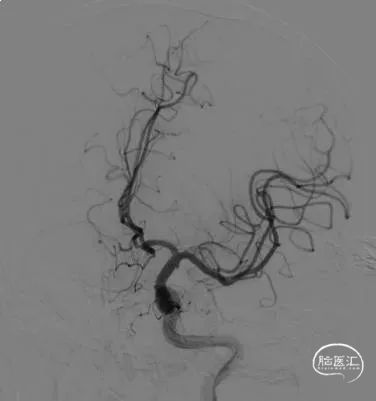

术前影像

栓塞过程

微导丝引导下,将微导管送入右侧大脑前动脉A1段,反复调整进入前交通动脉瘤内向下的分叶中,填入成篮圈后,依次置入若干枚Jasper®弹簧圈。支架半释放覆盖瘤颈,调整弹簧圈,稳定后解脱。